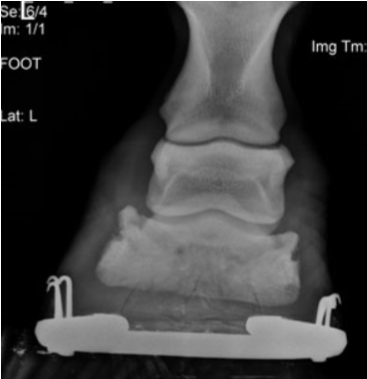

• what sign of laminitis can be seen in these images?

P3 drop / rotation as well as remodelling / degeneration at the tip of P3

• On radiography, rotation / dropping of P3, remodelling / degeneration at the tip of P3 may be seen and rarely collapse on just the lateral or medial side

• Rotation more than 5 degrees is mild, 5 to 10 degrees moderate and more than 10 degrees are severe